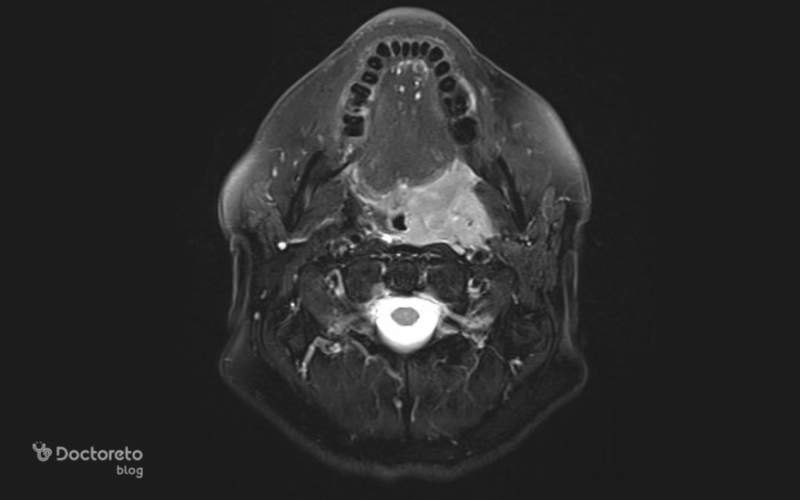

تصویربرداری از سرطان لوزه

تشخیص نهایی سرطان لوزه فقط با عکس ظاهری انجام نمیشود؛ بلکه تصویربرداری پزشکی نقش اصلی را دارد. CT scan، MRI و PET scan رایجترین روشها هستند. این تصاویر به پزشک کمک میکنند میزان درگیری بافت و گسترش احتمالی به غدد لنفاوی یا بافتهای اطراف را بررسی کند.

در مقایسه با عکسهای ساده دهانی، تصویربرداریهای پزشکی نمای بسیار دقیقتری از عمق و وسعت بیماری نشان میدهند. برای مثال PET scan میتواند برای بررسی گسترش کمککننده باشد و مشخص کند آیا سلولها سرطانی هستند یا نه. به دلیل همین دقت بالا، پزشکان هیچوقت تنها به عکس ظاهری اکتفا نمیکنند. تصویربرداری برای تعیین مرحله سرطان نیز ضروری است و میتواند مسیر درمان را کاملاً تغییر دهد.